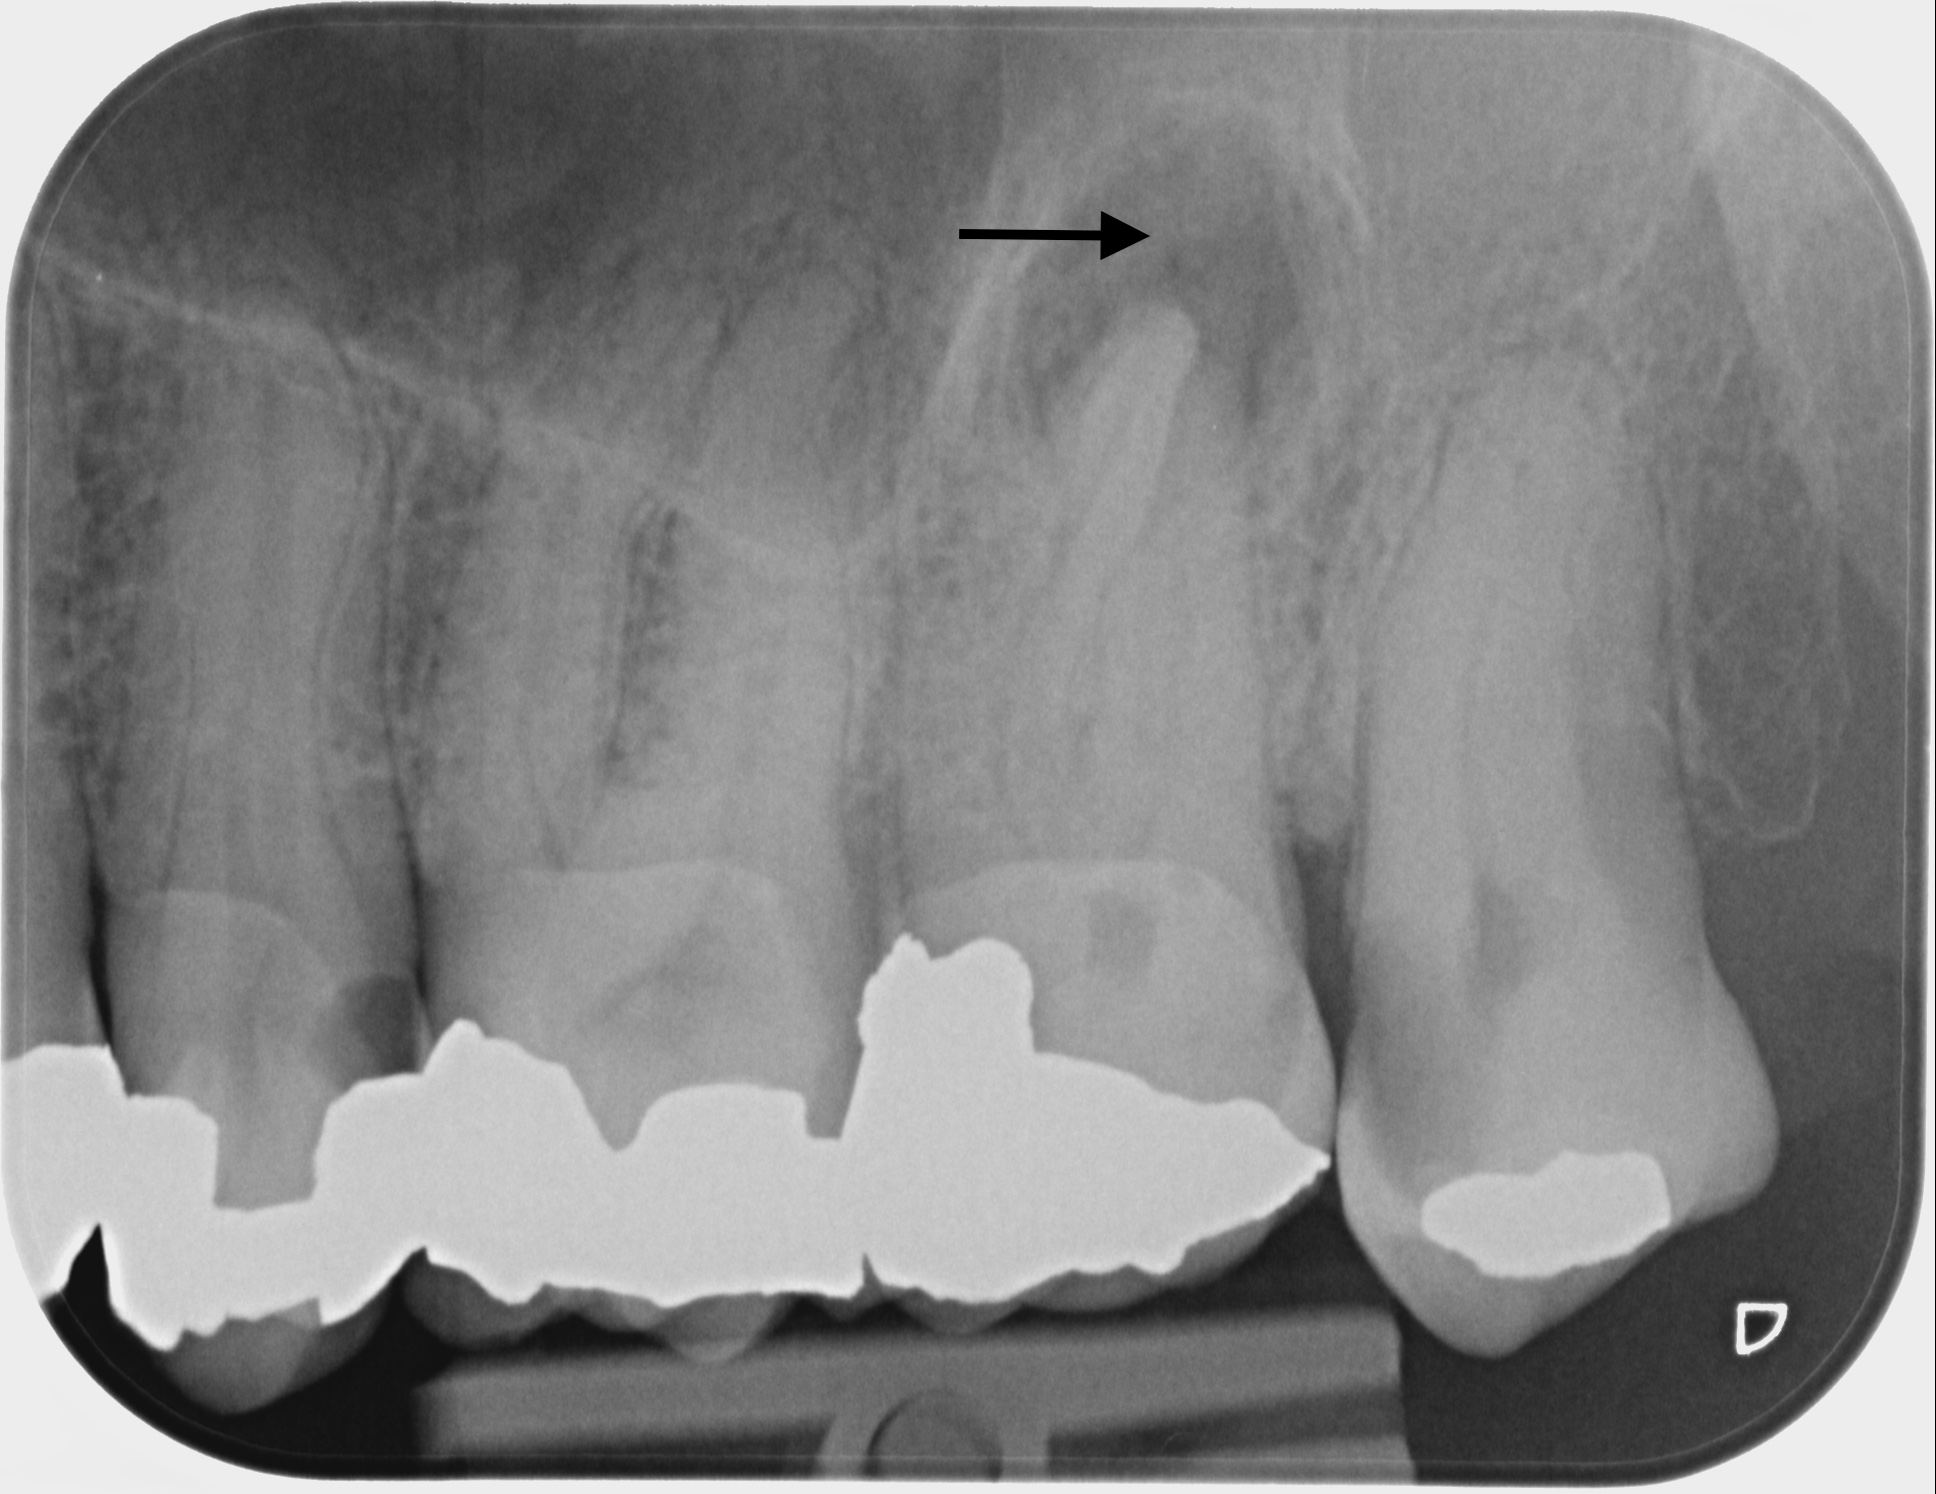

Dringen Bakterien in die Pulpa ein, entsteht eine Pulpitis (Entzündung des Zahnnervs). Mögliche Ursachen einer Pulpitis können eine tiefe Karies, nervnahe Füllungen, Zahnrisse, Frakturen, Trauma oder ein Spalt zwischen dem Zahn und der Füllung oder einer Krone sein.

Wird eine Entzündung nicht rechtzeitig behandelt, gelangen die Bakterien über die Wurzelspitze in den Kieferknochen und ein Abszess kann sich entwickeln.

Bei einer Wurzelbehandlung wird der erkrankte oder abgestorbene Zahnnerv entfernt. Die komplexen Wurzelkanalsysteme werden mit speziellen Feilen aufbereitet, gereinigt und gründlich desinfiziert. Anschliessend erfolgt eine bakteriendichte Füllung der Hohlräume im Wurzelbereich.

Fallbeispiele

Zum Vergrössern klicken